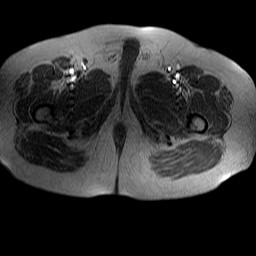

Esami: RMN BACINO

Evidenti e simmetriche alterazioni osteofitosiche in regione coxo femorale con riduzione delle rime articolari. Degenerazione completa del cercine glenoideo. Non attuali segni di versamento articolare. Non segni di edema osseo che escludono attuale algodistrofia od osteonecrosi. Lieve e simmetrica riduzione del trofismo della muscolatura glutea.